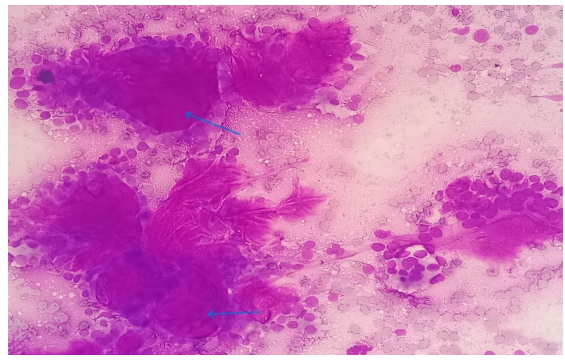

A 38 year old female presented with the complaints of pain and difficulty during swallowing and history of weight loss. Up on examination, a swelling was noted on the left side of her neck, which moved with deglutition. Ultrasound (USG) revealed a well circumscribed hypoechoic nodule measuring 3.2x2.1cm in the left lobe of thyroid with no extrathyroidal extension, however the nodule was compressing the esophagus. Fine needle aspiration was performed on the lesion and stained with Papanicolaou (PAP) stain and May Grunwald Geimsa (MGG) stains. The smears exhibited high cellularity with globoid clusters and three dimensional tissue fragments composed of aggregates of cells with central core of homogenous basement membrane material with cells having basaloid morphology and scant cytoplasm (Figure 2). MGG smears highlighted pink/ magenta amorphous basement membrane hyaline globules in the clusters of tumor cells (Figure 3). Cell block preparation of fine needle aspiration showed cribriform pattern of tumor cells with hyaline globules (Figure 4). Immunocytochemistry conducted on cell block shows TTF-1 positivity in normal thyroid follicles and negative staining in tumor cell clusters. CD117 and synaptophysin were inconclusive on cell block, but based on morphology this case was reported as adenoid cystic carcinoma of thyroid. Contrast-enhanced computed tomography (CECT) prior to surgery depicted a well defined heterogeneously enhancing hypodense lesion in the left lobe of thyroid measuring 3.2x2.1x1.7cm with no  additional lesions or abnormalities noted in the adjacent structures like trachea, larynx, oesophagus or upper mediastinum(Figure 1).  The excised left hemi-thyroidectomy specimen was received which showed a grey white solid homogenous lesion measuring 3.5x2.2x2cm reaching till the capsule. No cystic spaces/papillary projections/colloid seen in the lesion grossly. Adjacent thyroid parenchyma was normal. Histopathology sections showed tumor arranged in tubules and cribriform pattern along with hyaline globules suggesting the diagnosis of adenoid cystic carcinoma of thyroid, limited to thyroid without extra thyroid extension (Figure 5). IHC with CD117 showed cytoplasmic positivity in tumor cells further supporting the diagnosis (Figure 6).

Figure 3: MGG stained smears (20x) showing globoid clusters of basaloid cells with luminal hyaline globules(arrow).